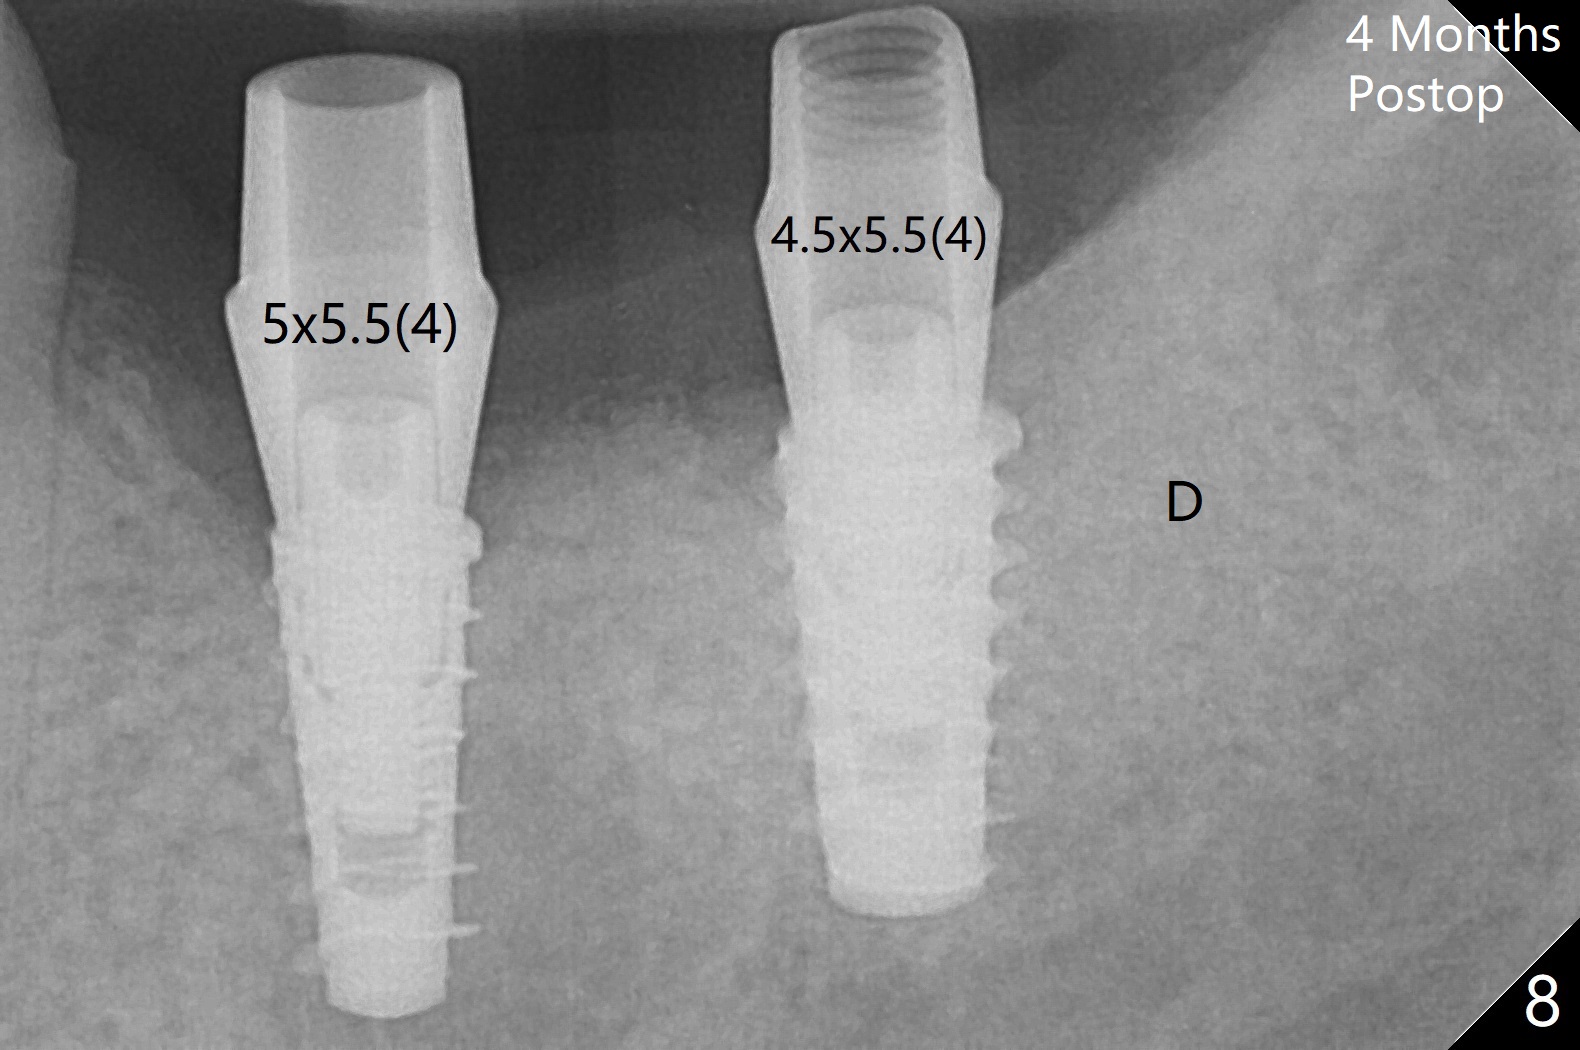

The female woman is afraid of pain. After placement of 4x9 mm FC implant at #19, infiltration anesthesia is not enough for osteotomy at #18. Block anesthesia is added. When a 5x9 mm FC implant is placed in the osteotomy (designed for 5x8.5 mm IS one), it is close to the Inferior Alveolar Canal (Fig.1 red dashed line; Fig.2 (*: bone graft with PRF)). The third contributing factor is the pressure upon the distal end of the distal end guide while osteotomy. A few hours later, the patient reports no paresthesia. The implant placement level and trajectory are normal at #18 and 19 (Fig.3-5). To check pair abutment seating with 30 Ncm torque, PA is taken after removal of healing abutments 4 months postop (Fig.6-8). First the cuff of the abutment is short, subgingival distal of #18 (Fig.6 * (gingiva)). When an abutment with longer cuff is placed, it appears to be close to the distal crestal bone (Fig.7 *). Finally a smaller abutment seams to be appropriate (Fig.8). Retrospectively the larger abutment (6.5x4(4) mm) is incompletely seated initially (Fig.1 with gap).